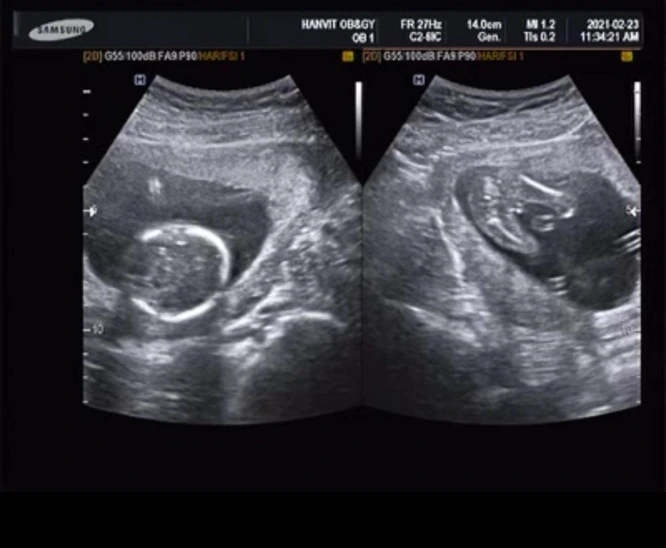

칠흑같이 어두운 우주,

그 안에 작은 콩알 하나가 콩-박혀있었다.

동생이 곧 아버지가 된단다. 철부지 막내가 처음으로 나보다 어른스럽게 느껴졌다. 생애 최초로 마주하는 경이로운 만남에 그는 매우 들떠 있었다. 목소리는 온통 설레임으로 가득했고, 나는 기꺼이 함께 기뻐해주었다.

전화를 끊고서 한동안 가만히 까만 바탕에 흰 자국만이 뜨문뜨문 보이는 사진을 들여다보았다.

광활한 우주에 겨우 자리 잡은 작은 점.

외로워 보였다. 그 안에서 홀로 얼마나 적막할까. 때로는 영영 나가지 못하게 될까봐 무섭기도 할 테지. 새삼 아직 세상에 나오지도 않은 작은 생명체로부터 묘한 동질감이 느껴졌다.

뱃속의 아가는 외롭다. 그래서 나 여기 있다고, 나를 좀 봐달라고, 발차기도 하고 입덧이란 것으로 존재를 증명한다. ‘괜찮아’. ‘안심하렴’ ‘사랑한다 아가야’. 우주의 주인인 엄마가 신호를 보낸다. 엄마의 바다에서 허우적거리는 아가에게 ‘탯줄’은 세상과의 강력한 연결고리다. 그것은 열 달이라는 고독한 항해를 지탱해주는 힘이 된다. 줄곧 나는 바다란 중성명사 ‘다스 메어(das Meer)’가 아닌 여성명사 ‘디 제(die See)’라고 생각해왔다. 그래서 바다가 마냥 망망대해처럼 느껴지지는 않았다. 나에게도 엄마가 있다. 탯줄처럼 연결되어 있는 친구들도, 인터넷 망으로 이어진 랜선 이웃도 있다. 분명 몇 번의 거친 항해를 거쳐 나의 바다로 돌아갈 수 있을 것이다. 이렇게 마음을 추스리다가도 독일이라는 나라에 산다는 것은 외롭다. 왜? 이 글의 주제는 결국 돌고 돌아 다시 ‘고독’이다. 고독이라는 것은 녹진하게 나를 따라다녔다. 용수철 마냥 잠시 눌려졌다 핑-핑- 솟아올라왔다